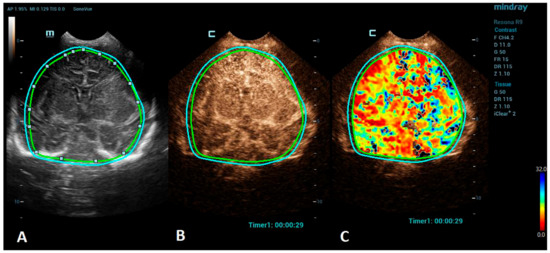

Figure 2.

A VueBox® analysis of a 5-day-old male with ischemic stroke in the territory of the left middle cerebral artery. (A) The coronal grayscale reference ultrasound image of the brain. (B) The coronal CEUS image. (C) The coronal CEUS perfusion map highlighting an increased fall time parameter in the territory of the left middle cerebral artery. The whole brain is selected as a region of interest in the presented image (marked by the two color lines).